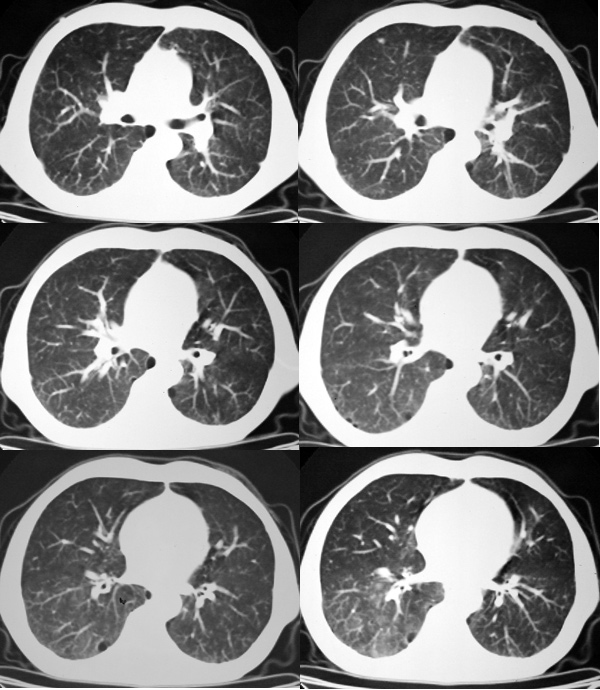

右肺囊实性占位 患者拒绝穿刺活检  近期始终间断性发高烧 使用消炎控制, 左鼻翼部有多发皮肤溃疡

双肺呈毛玻璃状,胸膜旁有多个小囊状气腔。右下囊实性病灶内有园形气体影,边缘光滑,与之相连的胸膜稍增厚,间断发热,抗炎效果不好。考虑机会性感染可能性大。

右下肺占位性病变,其边缘较光整无明显分叶,似有包膜,邻近胸膜无凹陷征及牵拉征象,包块内见数个大小不等气液面及不规则透亮影,纵隔未见明显淋巴结肿大。结合上次ct检查,考虑:炎性包块或真菌感染包块可能性大,周围型肺癌可能性小。

考虑右肺下叶慢性肺脓肿;不排除周围型肺癌。